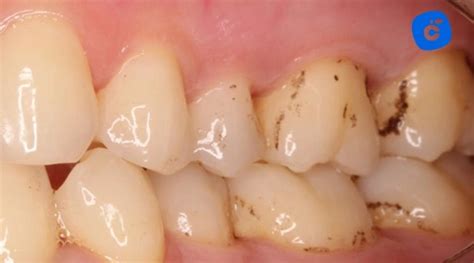

Las manchas negras en los dientes son decoloraciones oscuras (marrón oscuro o negras) que se adhieren al esmalte dental. Visualmente pueden verse como líneas cercanas a la encía, puntitos negros en la superficie o zonas oscurecidas en alguna pieza dental. En mi experiencia, estas pigmentaciones pueden tener diferentes causas. Algunas son simples tinciones externas por nuestros hábitos (como fumar o tomar café), y otras pueden indicar afecciones internas del diente (como una caries dental iniciándose).

- Acumulación de sarro (placa bacteriana calcificada): La placa bacteriana que no se elimina adecuadamente con la higiene diaria se endurece formando sarro (cálculo dental). El sarro inicialmente es amarillo o marrón claro, pero con el tiempo puede volverse muy oscuro. En algunos pacientes vemos un borde negro en la base de los dientes, justo donde tocan la encía: esa es la placa calcificada con pigmentos de alimentos y sangre. De hecho, el sarro subgingival (bajo la encía) suele tomar un color negro por absorber pigmentos sanguíneos en esa zona. Si notas manchas negras entre los dientes y la encía, es muy probable que sea sarro antiguo. Aunque tengas buena higiene, a veces hay zonas de difícil acceso donde el sarro se acumula. La solución es una tartrectomía, es decir, una limpieza dental profesional para eliminar todo ese cálculo. Recuerda: el sarro no se quita con cepillo en casa, solo con instrumental especializado en la clínica.